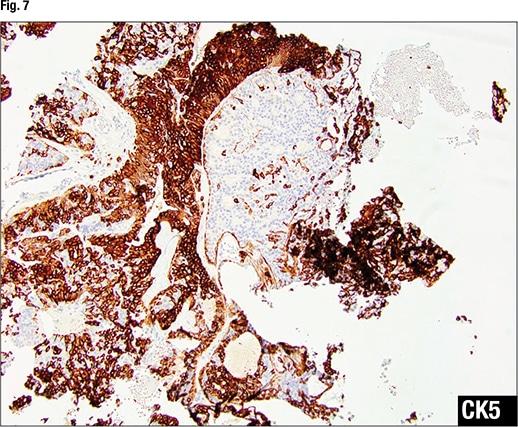

In Fig. 7 there is no CK5 staining in the area of ADH, “indicating this is a monoclonal proliferation.” In the area of UDH, “there’s a strong yet mosaic staining pattern of CK5, indicating a polyclonal proliferation.” ER staining in the area of ADH (Fig. 8) shows diffuse strong staining, indicating a monoclonal proliferation. In the area of UDH, the ER staining is focal with different intensity—some cells weak, others strong—indicating a polyclonal proliferation.